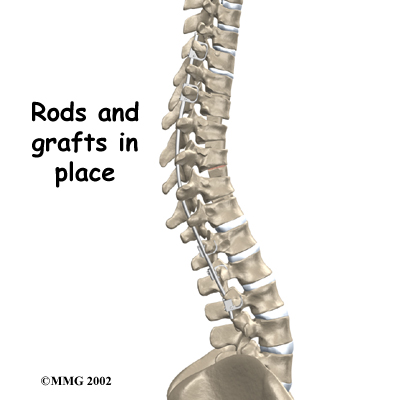

This surgery is done through the back (posterior) portion of the spine, as opposed to an anterior approach, which is done from the front. After making an incision in the back, the surgeon applies pressure to straighten the kyphosis. Small strips of bone graft are then laid over the back of the spinal column. These strips encourage the bones to grow together. Metal rods are attached along the spine to prevent the vertebrae from moving. The rods hold the spine in better alignment and protect the bone graft so it can heal better and faster.

The second part of the surgery is a more involved form of a posterior fusion using special rods and hooks. This part of the operation can be done right after the anterior fusion or scheduled for one week later.

For this part of the combined fusion surgery the surgeon makes an incision over the back of the spine. The skin and muscles are spread apart then strips of bone graft are laid across each vertebra to be fused. Long rods are inserted along the sides of the spine. The rods have hooks attached on both ends. Wire is wrapped between the top and bottom hooks. Tightening the wires causes the spine to straighten. The rods help hold the spine steady as the bone grafts heal. The rods are usually left in permanently.